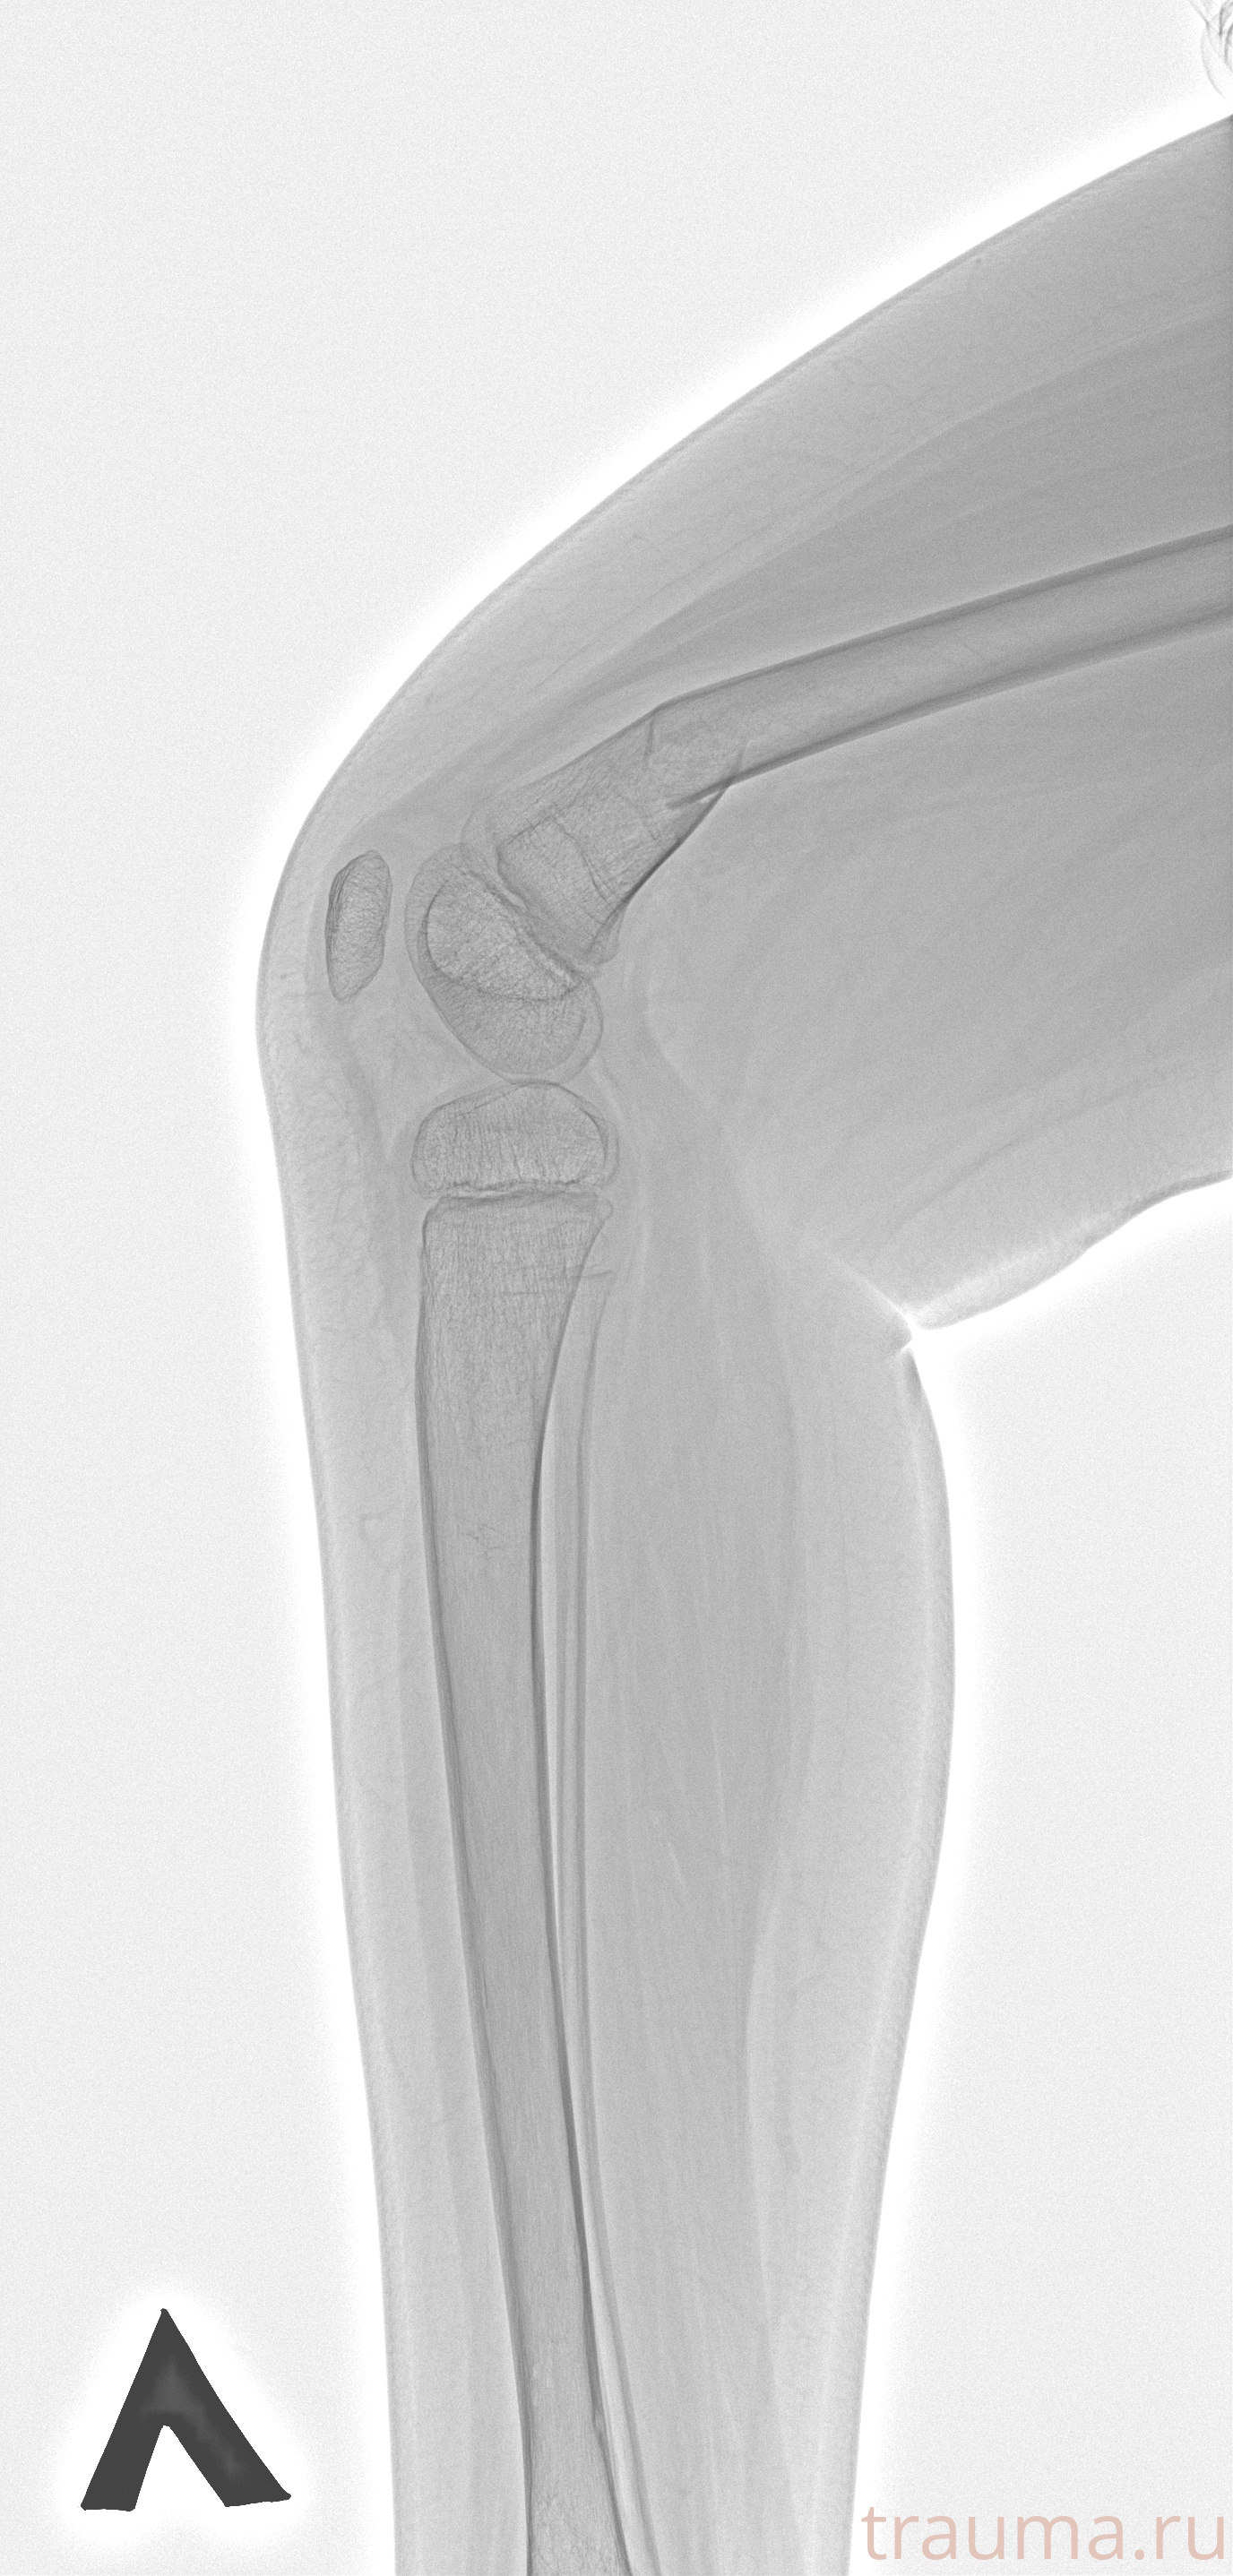

Рентген на дому: по вашему адресу приезжает врач-рентгенолог, травматолог-ортопед с мобильным рентгеновским аппаратом, проводит диагностику травмы или заболевания, делает необходимые рентгенограммы, дает рекомендации по дальнейшему лечению. Получить качественные снимки в домашних условиях возможно благодаря уникальной методике, разработанной МосРентген Центром для института  Склифосовского